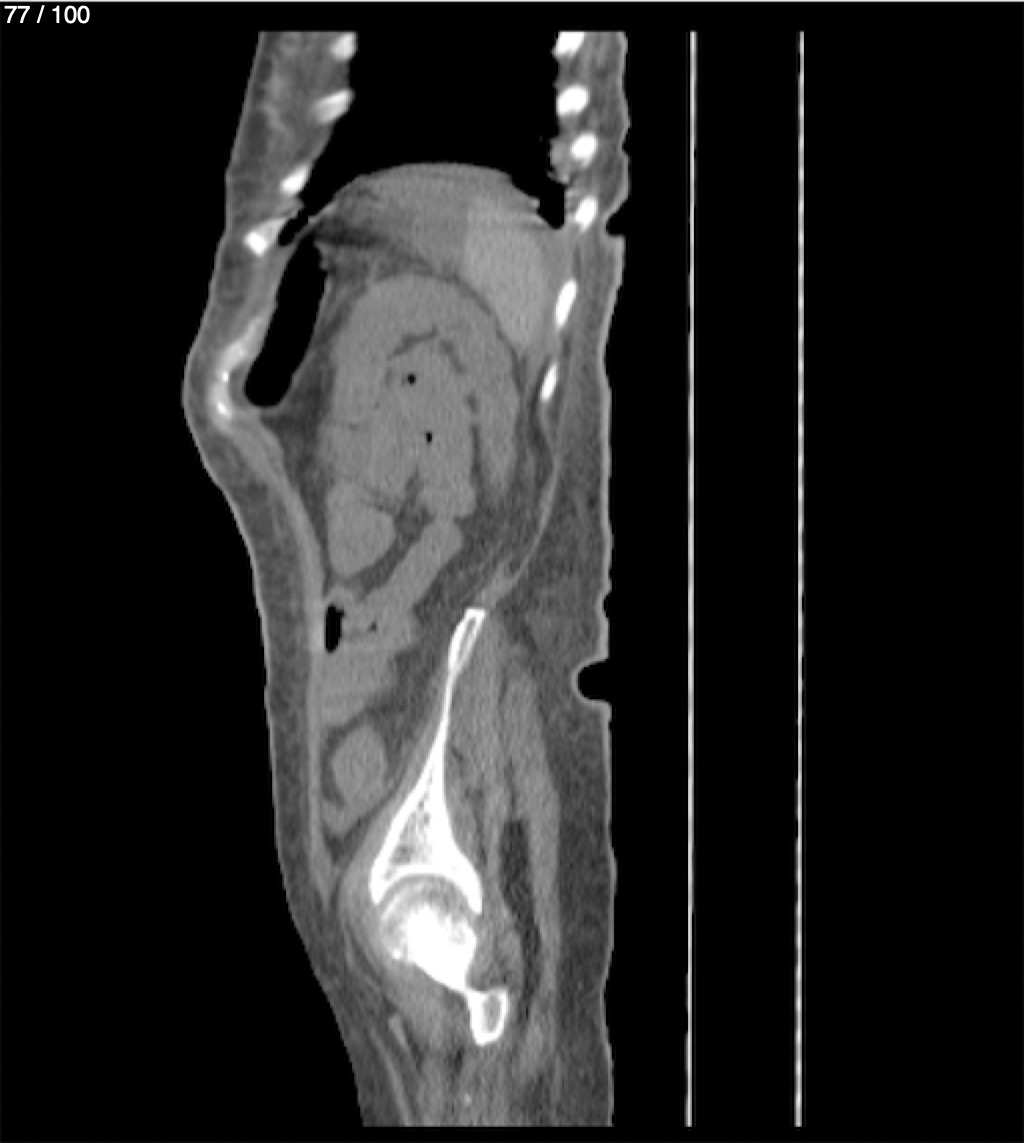

Hilda Geronimo Mendez 60A - T.C Abdomen Simple